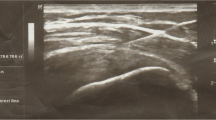

Patients were recruited from the outpatient clinic for shoulder pain and were selected when showing a focal hypoechoic or anechoic defect in the tendons on ultrasound (US) examination to diagnose RC tendinopathy. A linear probe (model no. 11 L-D, 3.0–12.0 MHz) in a US machine (Voluson E6®, Siemens, Munchen, Germany) was used for this examination.

Inclusion criteria were (1) persons aged 18 years and older; (2) RC tendinopathy confirmed by ultrasonographic finding; (3) patient agreement to stop medication associated with RC tendinopathy such as NSAIDs except the drugs given by the study for rescue medication; (4) had not undergone shoulder surgery within 3 months; (5) had not taken local steroid injection within 1 month or systematic steroid therapy within 2 weeks; (6) had neither infectious disease nor acute inflammatory disease such as local infection at the site of the procedure; and (7) gave written informed consent. RC tendinopathy was diagnosed when there was a focal hypoechoic or anechoic defect in the tendon of rotator cuff muscles [27].

Patients were in supine position with their arms placed on the superior aspect of the iliac wing with the palm up and the elbow flexed. We found the long head of biceps in the intertubercular groove transversely via ultrasound. After lining the probe along the long axis of biceps tendon, the probe was moved to the supraspinatus tendon in a parallel position. After finding the hypoechoic lesion, 2 ml of PRP solution was injected to the hypoechoic lesion of degenerative supraspinatus via 22-gauge syringe with peppering technique (Fig. 1). Peppering technique was used to avoid tendon morphology disruption by injecting PRP into the tendon [28]. The remaining 1 ml of PRP solution was used in analyzing the compositions of PRP.

Ultrasound assessment

Rotator cuff tendon integrity was evaluated by US imaging examination before and 24 weeks after the procedure. US examinations were performed with the patient seated on a backless chair. The patient was positioned with his/her arm placed posteriorly, placing the palmar side on the superior aspect of the iliac wing with the elbow flexed posteriorly. By positioning the transducer around the curvature of the humeral head in the transverse plane, the biceps was viewed in the osseous groove. Once located, the transducer was rotated until the biceps was viewed longitudinally. The transducer was moved in a parallel direction to show the long axis of the supraspinatus tendon. Thickness of the supraspinatus was measured at the greatest distance (mm) among the long axis images of the supraspinatus tendon.

Thickness of the supraspinatus in the PRP group decreased 6 months after PRP injection while thickness in exercise group slightly increased 24 weeks after exercise.

The thickness of the supraspinatus was decreased at 24 weeks after PRP injection but was increased at 24 weeks after exercise. Tendon thickness in degenerative tendinopathy was seen to be increased on ultrasound examination [39] and decreased after adequate treatment [40], which can explain our results. Tendon thickness is known to be increased after exercise [41], which also explains our results.